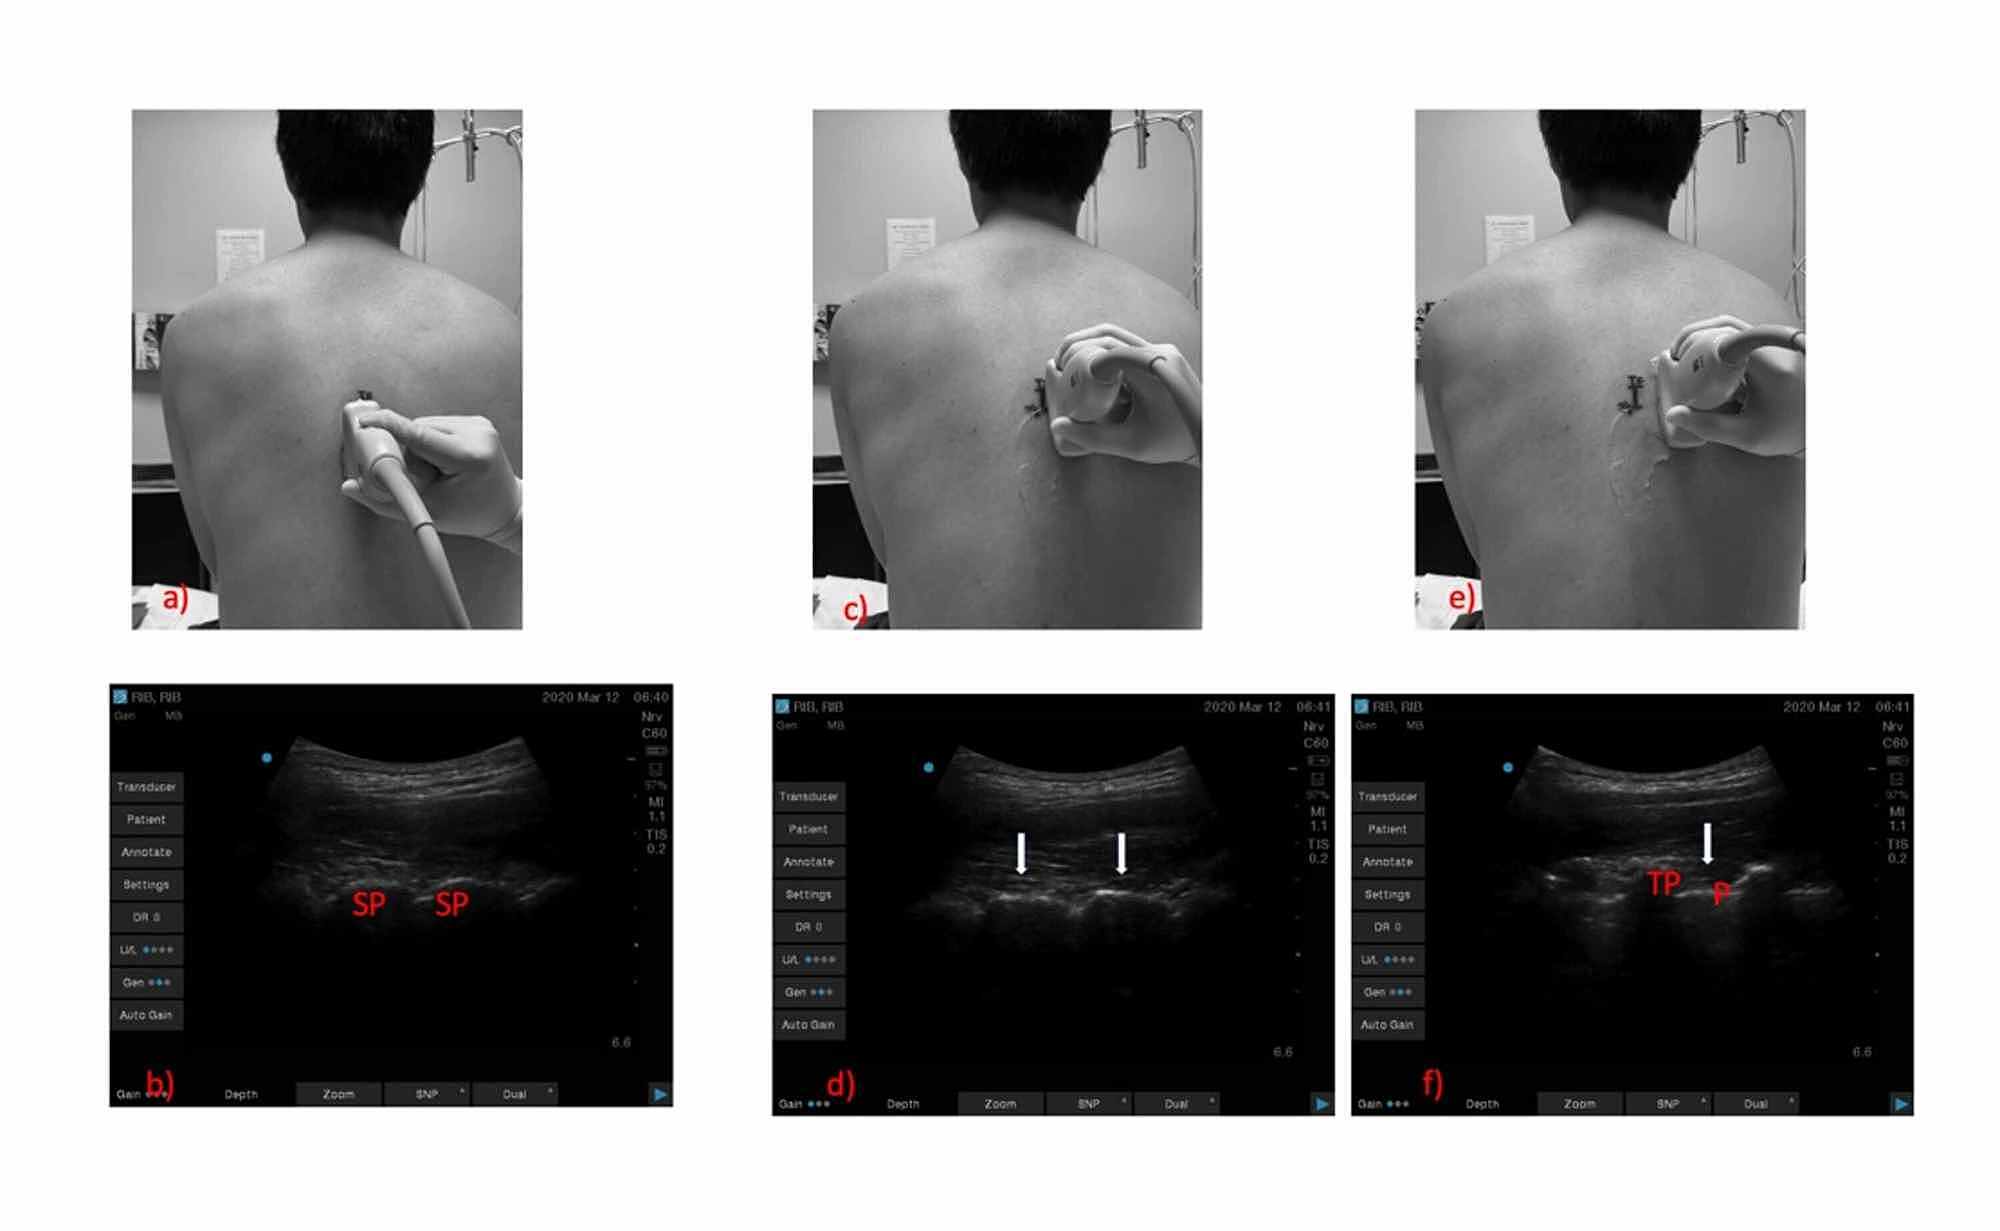

Efficacy of UltrasoundGuided Serratus Anterior Plane Block for Rib Fracture Block  Left pleura cavity (viewed from left) showing intercostal bundles (vein, artery, and nerve) under ribs. Rib fractures are common injuries that occur most often following blunt thoracic trauma but can also result from severe. 10 rows  paravertebral blocks are designed to deliver local anaesthetic to block both dorsal and ventral rami of spinal nerves in the paravertebral space (fig. Most. Rib Fracture Block.

Cureus The Challenges of Ultrasoundguided Thoracic Paravertebral Rib Fracture Block  Most common injury in blunt chest trauma. 10 rows  paravertebral blocks are designed to deliver local anaesthetic to block both dorsal and ventral rami of spinal nerves in the paravertebral space (fig. Rib fractures are common injuries that occur most often following blunt thoracic trauma but can also result from severe. The superficial serratus anterior plane block (sapb) is a. Rib Fracture Block.

Erector spinae plane block for pain relief in rib fractures British Rib Fracture Block  The most important aspects of management are multimodal analgesia, including regional anaesthesia and ventilatory support. This module outlines the ultrasound guided technique. Rib fractures are common injuries that occur most often following blunt thoracic trauma but can also result from severe. Most common injury in blunt chest trauma. Serratus anterior plane block can be used as multimodal analgesia for rib. Rib Fracture Block.